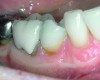

Fig 4. Severe recession visible on teeth Nos. 29 and 30.

Figure 4

Fig 5. Teeth Nos. 29 and 30 following connective tissue grafting showing minimal recession and improved tissue health.

Figure 5

The presence of keratinized tissue around teeth and implants and its role in periodontal maintenance is somewhat controversial. It has been suggested that 2 mm of keratinized tissue is important to maintain gingival health around teeth.16 Minimal recession also facilitates maintenance by the therapist and plaque control by the patient (Figure 4 and Figure 5). Keratinized tissue around implants is also important. Chung et al17 completed a retrospective study examining the barrier function of keratinized tissue around dental implants. They examined 339 endosseous dental implants in place for at least 3 years in 69 patients and found that when an adequate band of keratinized tissue was present, less inflammation and plaque accumulation occurred (Figure 6 and Figure 7). Although there was no correlation to bone loss, there was improved comfort while cleaning the sites with keratinized tissue versus those areas that lacked keratinized tissue.